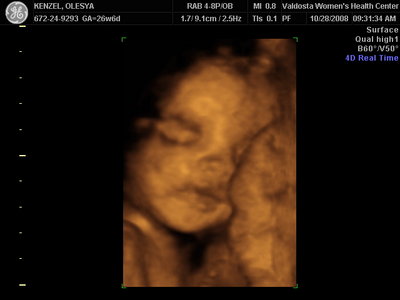

Ксюнь, а мы вообще не поняли. Она на всех фотках разная, да еще размытость такая. Пуповина то на носу болталась, то руками-ногами закрывалась. Главное что четкости нет совсем. Лоб у мужа тоже большой, а носы и губы зачастую на 3Д-4Д выходят разамазанно-пухло-приплюснутыми Поставлю для наглядности фотку моей средней-Джианки с 3Д УЗИ, там видно черты намного лучше и она на себя ту похожа сейчас, хотя родилась мне совсем на фото УЗИ не казалась похожей.

KENZEL,OLESYA_3.JPG [ 56.84 КБ | Просмотров: 1422 ]